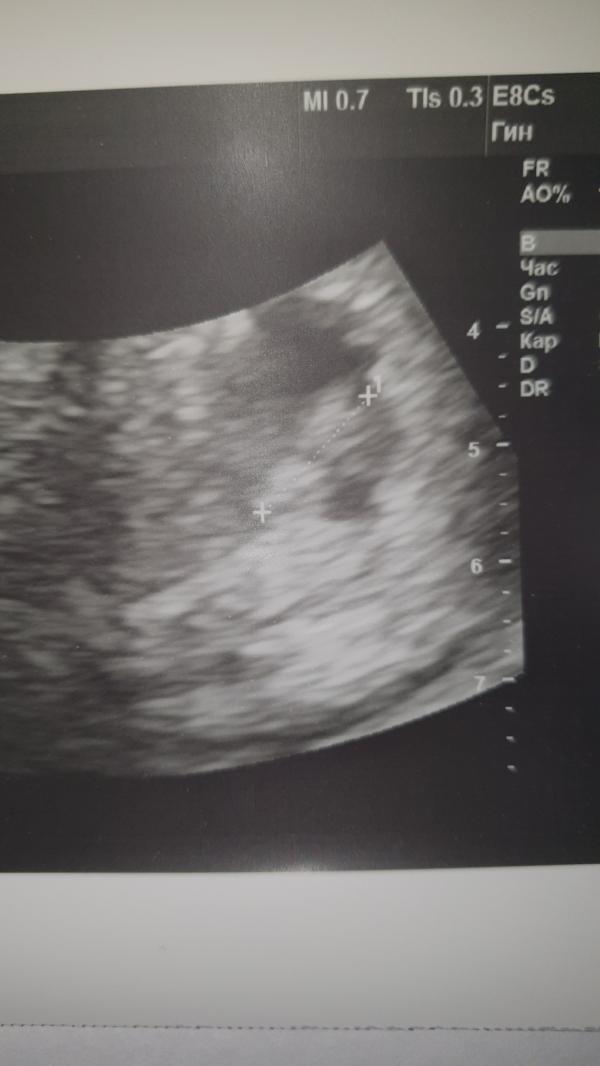

Вот и всё закончилось😥🤰🙏 8.3 недели...... моя бусинка погибла внутри меня уже 5-7 дней назад🙏 Причем погиб где-то на следующий день, когда меня выписали из роддома. Сейчас пришла с УЗИ....замершая, за 8 дней всего на 1мм подросло плодное яйцо,оно уже ОЧЕНЬ деформировано, у эмбриона ВООБЩЕ нечеткие границы, а это значит,что он начал разлагаться, также есть 2 отслойки,которые давали мазню,но почему то в роддоме их "не видели" 🤦🏻♀️Предположили, что наркоз мог повлиять на развитие, либо другие факторы, может естественный отбор 🤔 На всё воля Божья🙏 не суждено было этому малышу появиться у нас в семье🙏 Я морально уже была готова к любому исходу, очень жалко.....очень....но я уже не в силах ничем ему помочь 😭😢🥺🙏 Завтра на чистку направление дали🥺🙏 берегите своих малышей и себя🙏 ЗАВТРА 14 ФЕВРАЛЯ-День Влюблённых 🤦🏻♀️а я на чистку🤦🏻♀️